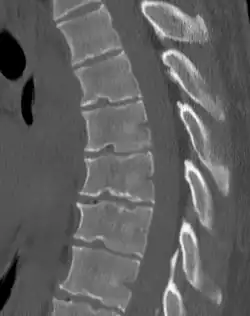

Scheuermann's disease is a skeletal disorder.[3] It describes a condition where the vertebrae grow unevenly with respect to the sagittal plane; that is, the posterior angle is often greater than the anterior. This uneven growth results in the signature "wedging" shape of the vertebrae, causing kyphosis. It is named after Danish surgeon Holger Scheuermann.[4][5][6]

Diagnosis is typically by medical imaging. The degree of kyphosis can be measured by Cobb's angle and sagittal balance.